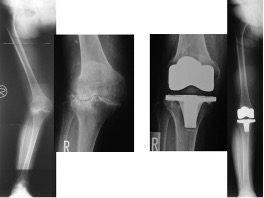

人工膝関節全置換術(TKA)・人工膝関節内側置換術(unicompartmental knee arthroplasty: UKA)

TKAはおもにOA(図2,3)やRA(図4)、UKAは骨壊死(図5)やOAの内側罹患例に行います。左右罹患例には両膝同日手術も施行しています(図3)。手術の目的は除痛、膝関節機能の回復によるADL、QOLの改善です。

人工膝関節は多機種ありますが、当科では自家組織(骨や靭帯)温存に配慮して、主に前十字靭帯のみ切除するCR型を選択し、膝蓋骨は非置換、セメントレス用コンポーネントを用いています(図2)。後療法は両側例でも翌日から離床と荷重を許可し、入院加療は約2週間です。

図2 片側TKA

図3 両側OAに対する両側同日TKA

図4 RAに対するTKA

図5 大腿骨内側顆部骨壊死に対するUKA